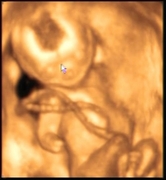

Плод 18 Недель Фото

Плод 18 Недель Фото 112 фото